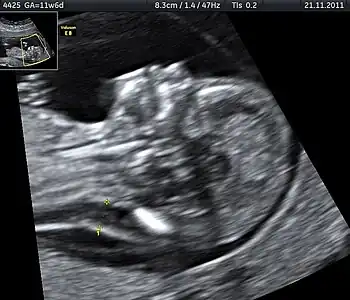

| Ultrasound is often used to diagnose stillbirth and medical conditions that raise the risk. | |

Often the cause is unknown.[1] Causes may include pregnancy complications such as pre-eclampsia and birth complications, problems with the placenta or umbilical cord, birth defects, infections such as malaria and syphilis, and poor health in the mother.[2][3][8] Risk factors include a mother's age over 35, smoking, drug use, use of assisted reproductive technology, and first pregnancy.[4] Stillbirth may be suspected when no fetal movement is felt.[5] Confirmation is by ultrasound.[5]

It is unknown how much time is needed for a fetus to die. Fetal behavior is consistent and a change in the fetus' movements or sleep-wake cycles can indicate fetal distress. A decrease or cessation in sensations of fetal activity may be an indication of fetal distress or death, though it is not entirely uncommon for a healthy fetus to exhibit such changes, particularly near the end of a pregnancy when there is considerably less space in the uterus than earlier in pregnancy for the fetus to move about. Still, medical examination, including a nonstress test, is recommended in the event of any type of any change in the strength or frequency of fetal movement, especially a complete cease; most midwives and obstetricians recommend the use of a kick chart to assist in detecting any changes. Fetal distress or death can be confirmed or ruled out via fetoscopy/doptone, ultrasound, and/or electronic fetal monitoring. If the fetus is alive but inactive, extra attention will be given to the placenta and umbilical cord during ultrasound examination to ensure that there is no compromise of oxygen and nutrient delivery.